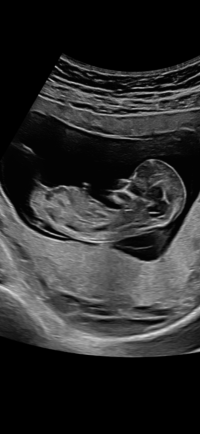

Gløymde å skrive at det var i veke 11+6

Jeg tror jente, ligner veldig på nuben til jenta vårNoen som vil prøve seg på gjetting hvis nub vises? Jeg har hatt sterk magefølelse to tidligere graviditeter. Denne gangen er jeg mer usikker

Det er for tidlig for nubtheory, frem til 12+3 ser alle like ut. Dvs alle ser ut som jenterGløymde å skrive at det var i veke 11+6![]()

Har du noe bilde av det? Hvis du vil deleJeg tror jente, ligner veldig på nuben til jenta vår